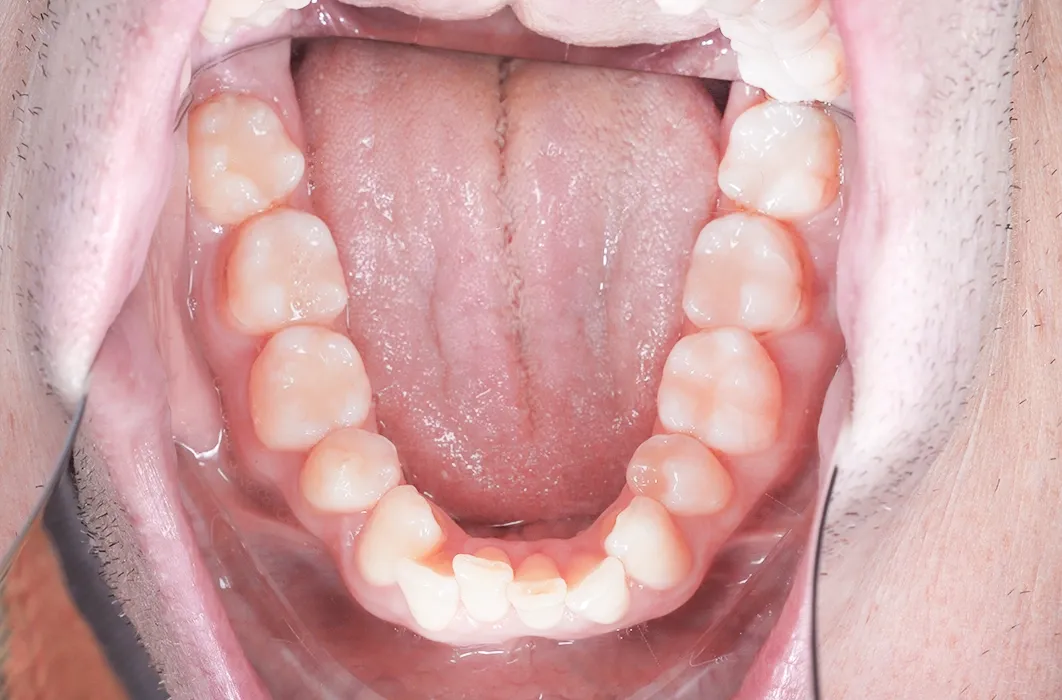

On his first visit, Mr C’s back teeth showed:

- Plaque buildup and staining across multiple areas.

- Visible tooth wear and cavities, especially on the molars.

- Severe decay on his upper left molar (tooth 27) and lower left molar (tooth 38).

- Old amalgam fillings that had discoloured and were no longer providing full protection.

The condition of the teeth made intervention necessary to maintain stability and function.